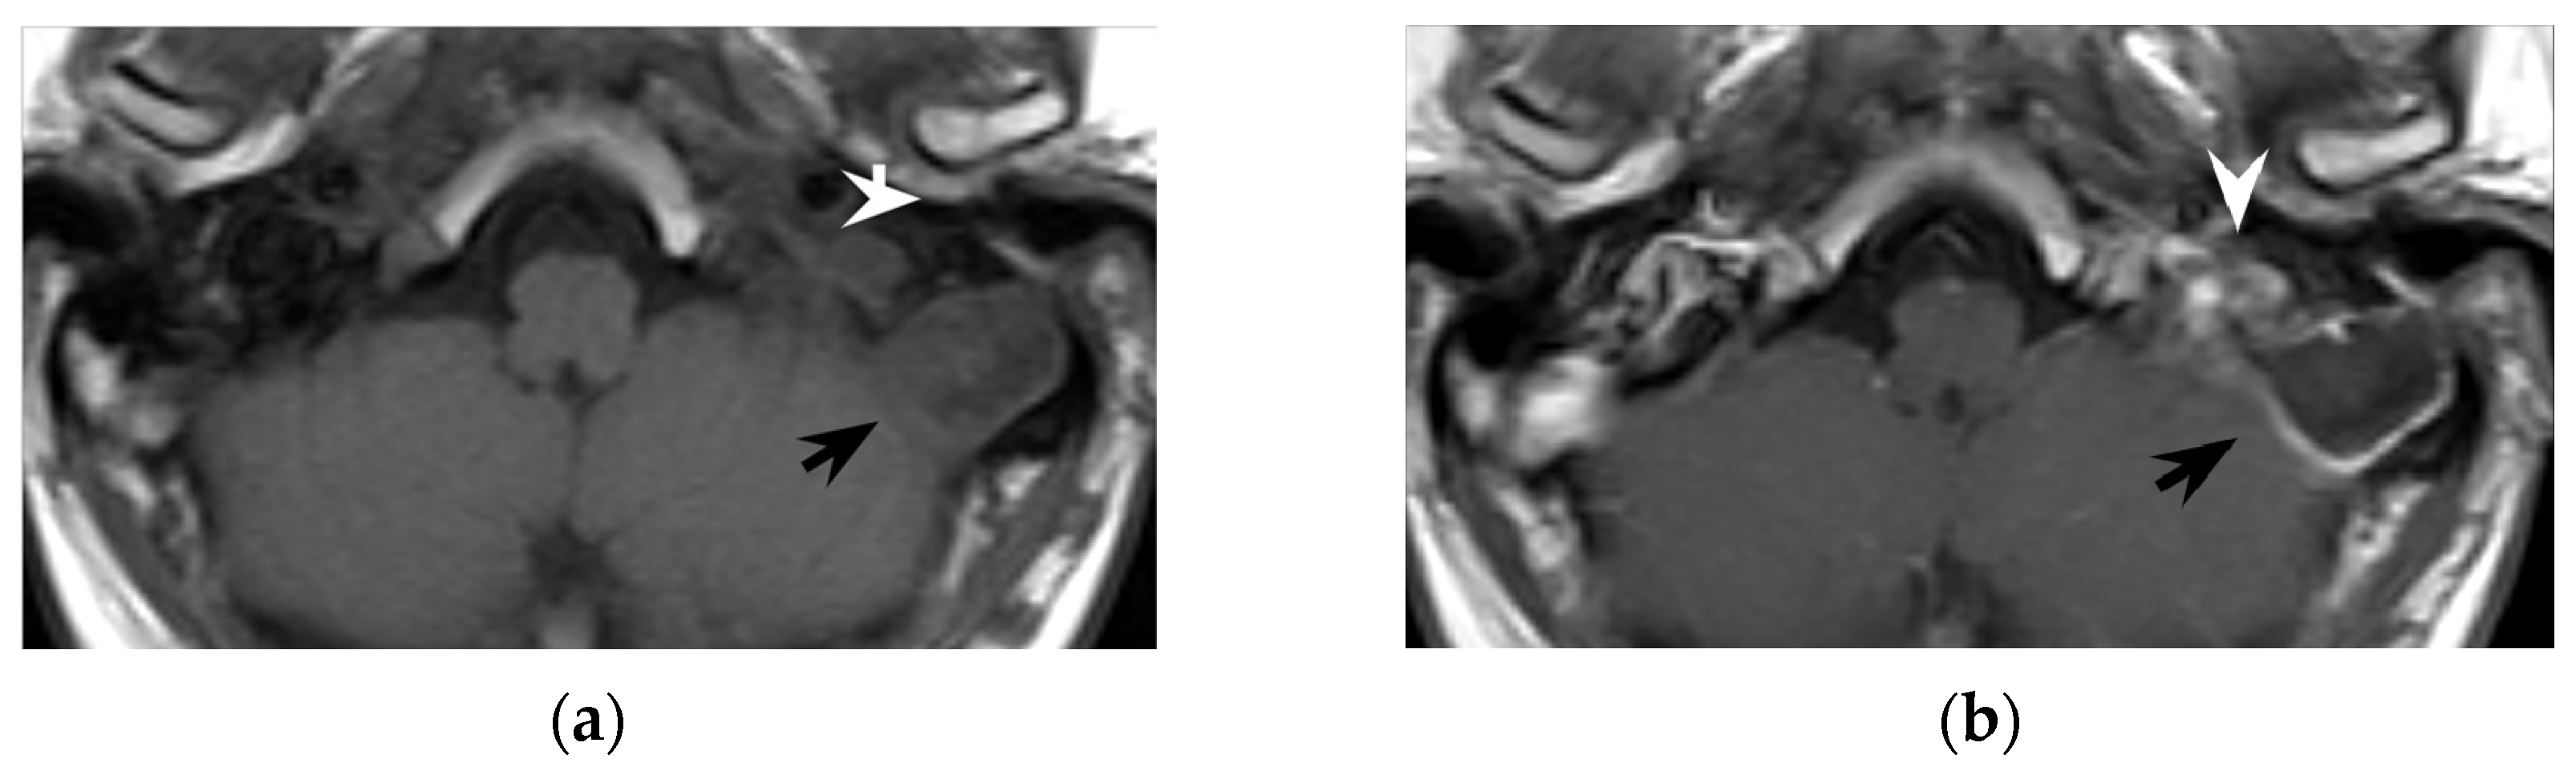

In the literature, cholesteatoma ipsilateral to Bezold’s abscess was reported in around 40% of patients. Cholesteatoma likely favors repeated mastoid bacterial superinfections and facilitates, by bone erosion, the spread of suppurative process into the neck (see Section 4.2). In several patients, cholesteatoma was diagnosed at surgery (11/97) and in a few cases it was partially an unexpected finding. However, MRI might easily recognize cholesteatoma preoperatively as these cysts appear as strikingly hyperintense DWI ovoid masses [42]. Differently from purulent collections, apparent diffusion coefficient (ADC) values might be slightly increased in cholesteatomas, suggesting a T2 shine-through effect more than a true water diffusion restriction [55]. From a technical point of view, whereas investigating the mastoid and the upper neck, non-echo-planar (non-EPI) DWI sequences should be preferred to minimize mastoid air/bone susceptibility artifacts that could mask the cholesteatoma [56]. DWI represents a very powerful tool also in postoperative and follow-up examinations, allowing for the detection of small cholesteatomatous residuals or recurrences (Figure 6), especially those with a diameter larger than 2–4 mm [57].

Figure 6. Thirty-seven-year-old man with chronic otitis media and history of ear surgery. MRI T1w (a) and contrast-enhanced T1w (b) sequences showing hypo-isointense material in the left mastoid (black arrows) spreading in the neck, in the posterior cervical space (white arrowheads). Note the mastoid mucosal enhancement, suggestive for mastoiditis, and the peripheral enhancement of the neck component (b). The material in the mastoid is hyperintense in diffusion-weighted imaging (c) and shows inhomogeneous apparent diffusion coefficient values (d), consistent with purulent collection and cholesteatoma. Bezold’s abscess and left mastoid cholesteatoma were confirmed at surgery.